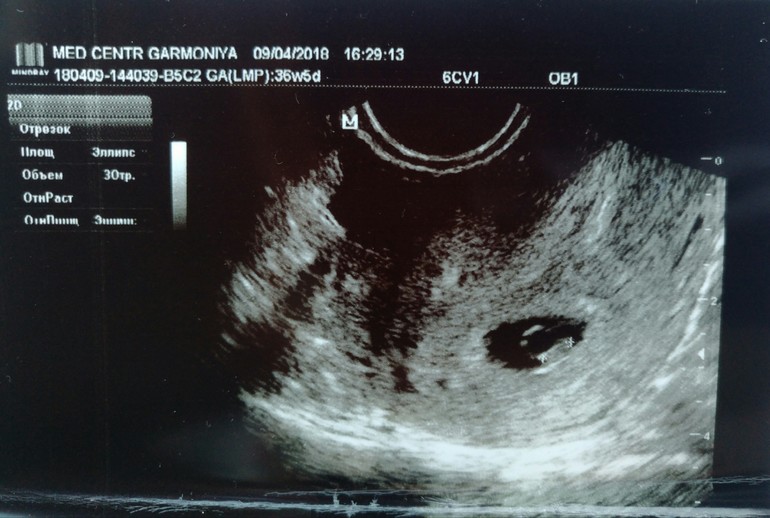

Тааак а теперь тадааам!!! Поехали мы переделать УЗИ платно...посмотрели кровоток, показали "кардиограмму" сердечка, эмбрион 4.6 мм, все на месте и соответствует сроку 6 недель!!!!!!

УЗИ эмбрион 4.6 мм плодное яйцо 8-1.3 мм

желточный мешочек 3.7 мм хорион кольцевидный

Но вот что значит платно...2000 руб и заключение беременность развивается в норме. Слава Богу за всё!